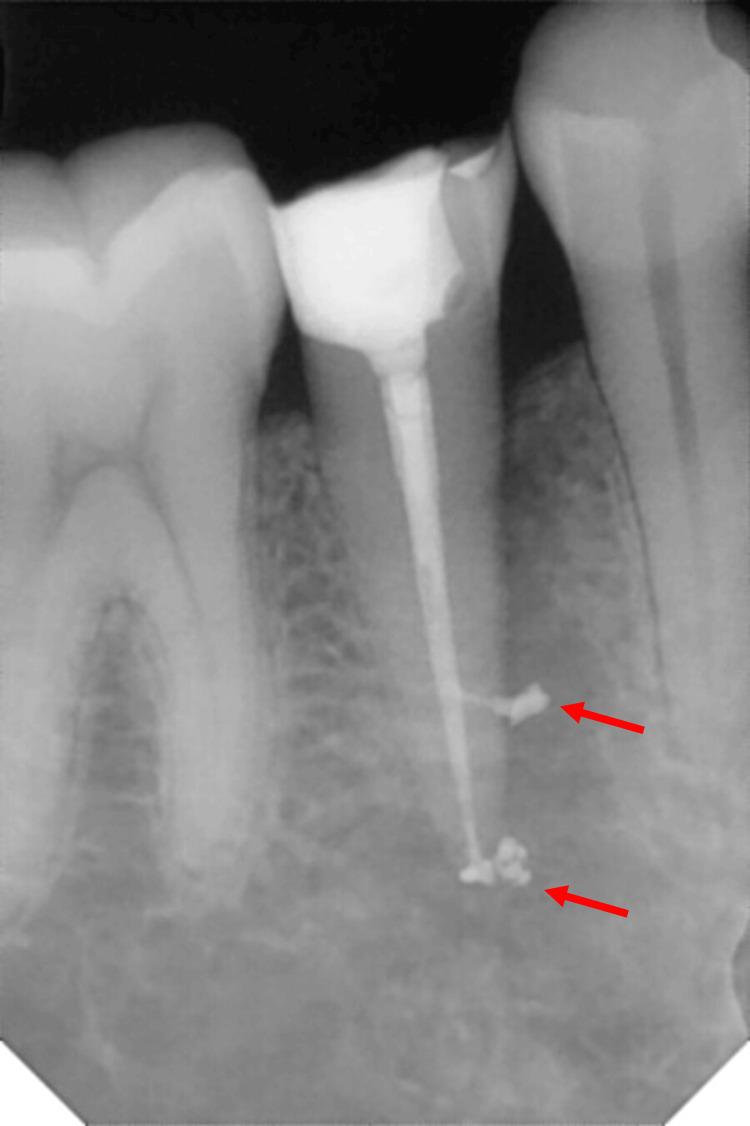

Hundred patients requiring root canal treatment in single-rooted teeth diagnosed with symptomatic irreversible pulpitis, with or without symptomatic apical periodontitis, were recruited. Pre-operative pain levels were recorded using the visual analog scale. Patients were randomized into four sealer groups (Tubli-Seal: Kerr Endodontics, California; AH Plus: Dentsply Sirona, Charlotte; BioRoot RCS: Septodont Healthcare India Pvt. Ltd., Maharashtra, India; and Nishika Canal Sealer BG: Nippon Shika Yakuhin, Shimonoseki, Japan). A single operator performed the treatment in a single visit, using the crown-down technique with Hand Protaper instruments (Dentsply Tulsa Dental, Tulsa), irrigation with 3% sodium hypochlorite (Dentpro, Mohali, India), 17% ethylenediaminetetraacetic acid (EDTA) (MD-Cleanser, EDTA Solution, Meta Biomed, Korea), and distilled water, followed by obturation using the cold lateral condensation technique. Post-operative pain levels were recorded at 24 hours, 72 hours, and seven days. The Kruskal-Wallis H test was employed to compare the pre- and post-operative pain scores across the groups.

Post-operative pain, apical extrusion, and radiopacity showed no statistically significant differences among the four sealer groups (p > 0.05). However, BioRoot RCS had the lowest pain levels at 24 and 72 hours, Tubli-Seal showed the least apical extrusion, and AH Plus and BioRoot RCS exhibited higher and comparable radiopacity.

招募了100例诊断为有症状的不可逆性牙髓炎、伴或不伴有症状性根尖周炎的单根牙需要进行根管治疗的患者。使用视觉模拟量表记录术前疼痛水平。患者被随机分为四个封闭剂组(Tubli-Seal:美国加利福尼亚州Kerr牙髓病公司;AH Plus:美国北卡罗来纳州夏洛特市登士柏西诺德公司;BioRoot RCS:印度马哈拉施特拉邦Septodont Healthcare印度私人有限公司;Nishika根管封闭剂BG:日本下关市日本狮王齿科医药品公司)。由一名操作者在一次就诊中进行治疗,采用冠向下技术,使用手用Protaper器械(美国俄克拉荷马州塔尔萨市登士柏西诺德塔尔萨牙科公司),用3%次氯酸钠(印度旁遮普邦莫哈利市Dentpro公司)、17%乙二胺四乙酸(EDTA)(韩国Meta Biomed公司MD-Cleanser,EDTA溶液)和蒸馏水冲洗,然后采用冷侧方加压技术进行根管充填。在术后24小时、72小时和7天记录术后疼痛水平。采用Kruskal-Wallis H检验比较各组术前和术后疼痛评分。

四个封闭剂组之间的术后疼痛、根尖挤出和不透射线性在统计学上无显著差异(p>0.05)。然而,BioRoot RCS在24小时和72小时时疼痛水平最低,Tubli-Seal根尖挤出最少,AH Plus和BioRoot RCS表现出较高且相当的不透射线性。